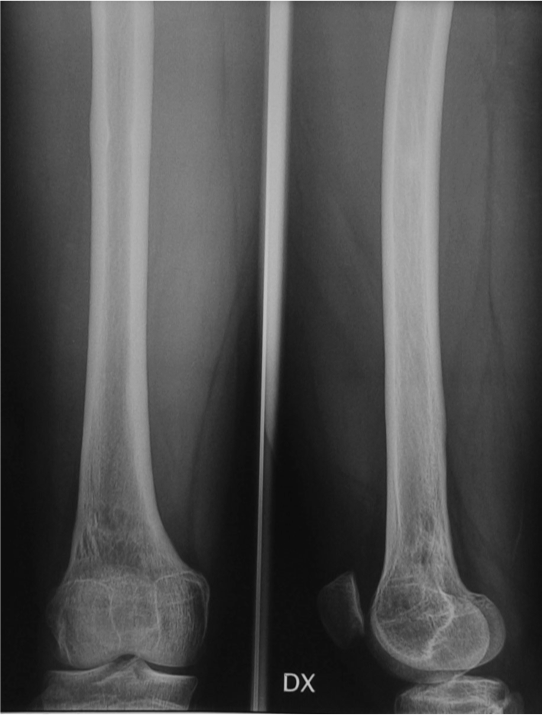

Maschio 13 anni. Esiti di frattura epifiolisi di condilo femorale esterno in eta di 10 anni.

Deformita in valgo del femore e accorciamento di 2,5 cm.